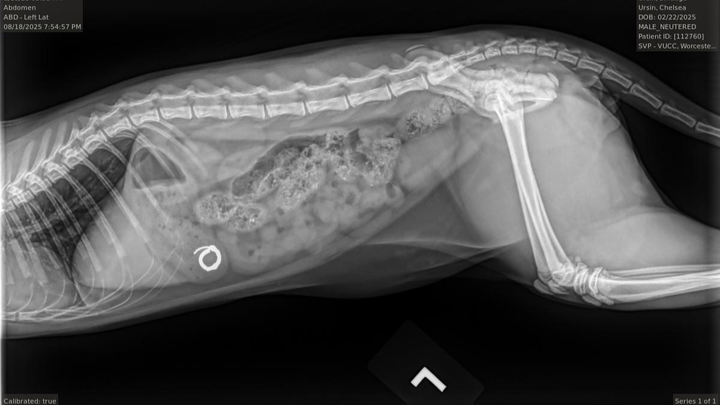

On the night of Sunday, August 17th, Smudge was cuddling with us in bed before we went to sleep. He started licking Chelsea's ear, and before she knew what had happened, he had somehow dislodged her hoop earring and swallowed it straight down his throat. After frantically checking the area around our bed and sifting through his poops the next morning, we took him to urgent care to get radiographs, and the results confirmed the worst. He had swallowed the whole earring, and it was currently resting in his stomach.

Today, August 20th, Smudge is at the Tufts Cummings School of Veterinary Medicine waiting to go under general anesthesia and have an endoscope put down his throat to hopefully remove the earring before it passes into his GI tract. Should it pass into his GI tract, a more invasive surgery may be required, and it could result in damage to his internal organs.